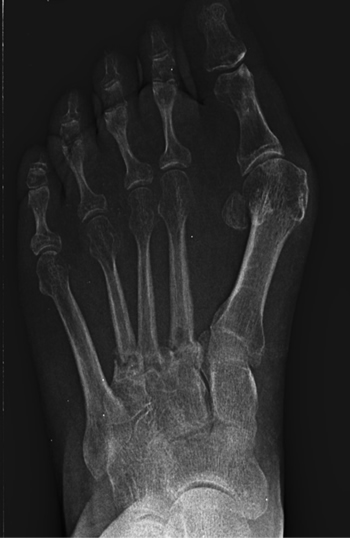

Se realizó radiografía dorso-plantar en carga del pie derecho (Figura 1) que mostraba una imagen radiológica compatible con ausencia de consolidación de las osteotomías en las bases de 2.º, 3.º y 4.º metatarsianos, además de la presencia de hallux abductus valgus. Se solicitó una tomografía axial computarizada (TAC) para estudiar más detenidamente el estado actual del proceso de consolidación ósea. La paciente acudió con resultado de TAC el 5 de mayo de 2015, donde se evidenció la ausencia completa de consolidación ósea en segundo metatarsiano (Figuras 2A y 2B), consolidación prácticamente completa de tercer metatarsiano (Figura 2C) y la presencia de callo óseo con consolidación incompleta en el cuatro metatarsiano (Figura 2D).

Figura 1. Radiografía dorso-plantar en carga del pie derecho. Se evidencia la ausencia de consolidación de las osteotomías en las bases de 2.º, 3.º y 4.º metatarsianos después de 9 meses de la intervención inicial.

Figura 2. Radiografía dorso-plantar en carga del pie derecho. Se evidencia la ausencia de consolidación de las osteotomías en las bases de 2.º, 3.º y 4.º metatarsianos después de 9 meses de la intervención inicial.